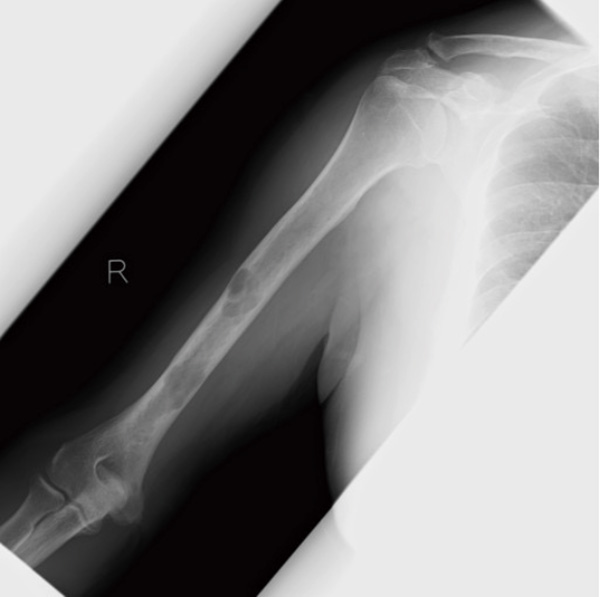

がんは進行すると全身のさまざまな臓器に転移しますが、骨は転移しやすい臓器の一つです。骨転移は主に肺がん、乳がん、前立腺がんでみられますが、疼痛、病的骨折、脊髄圧迫による神経障害、高カルシウム血症などさまざまな合併症を起こします。その結果、がん治療が続けられず治療成績を悪化させたり、本人の生活の質(QOL)を低下させうる、注意すべき病態です。

骨転移を抑制するためには、もとのがんの治療とあわせて、支持療法として骨修飾薬の適切な使用が重要です。ビスフォスフォネート薬であるゾレドロン酸(ゾメタ®)および抗RANKLモノクローナル抗体製剤であるデノスマブ(ランマーク®)が使用されます。日本ではいずれも悪性腫瘍の骨転移または多発性骨髄腫の骨病変に保険承認となっていますが、多発性骨髄腫では抗腫瘍効果(がんの抑制効果)も示されており、より積極的に導入されます。